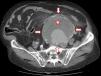

Abdomen agudo de presentación atípica

Acute abdominal pain with atypical presentation